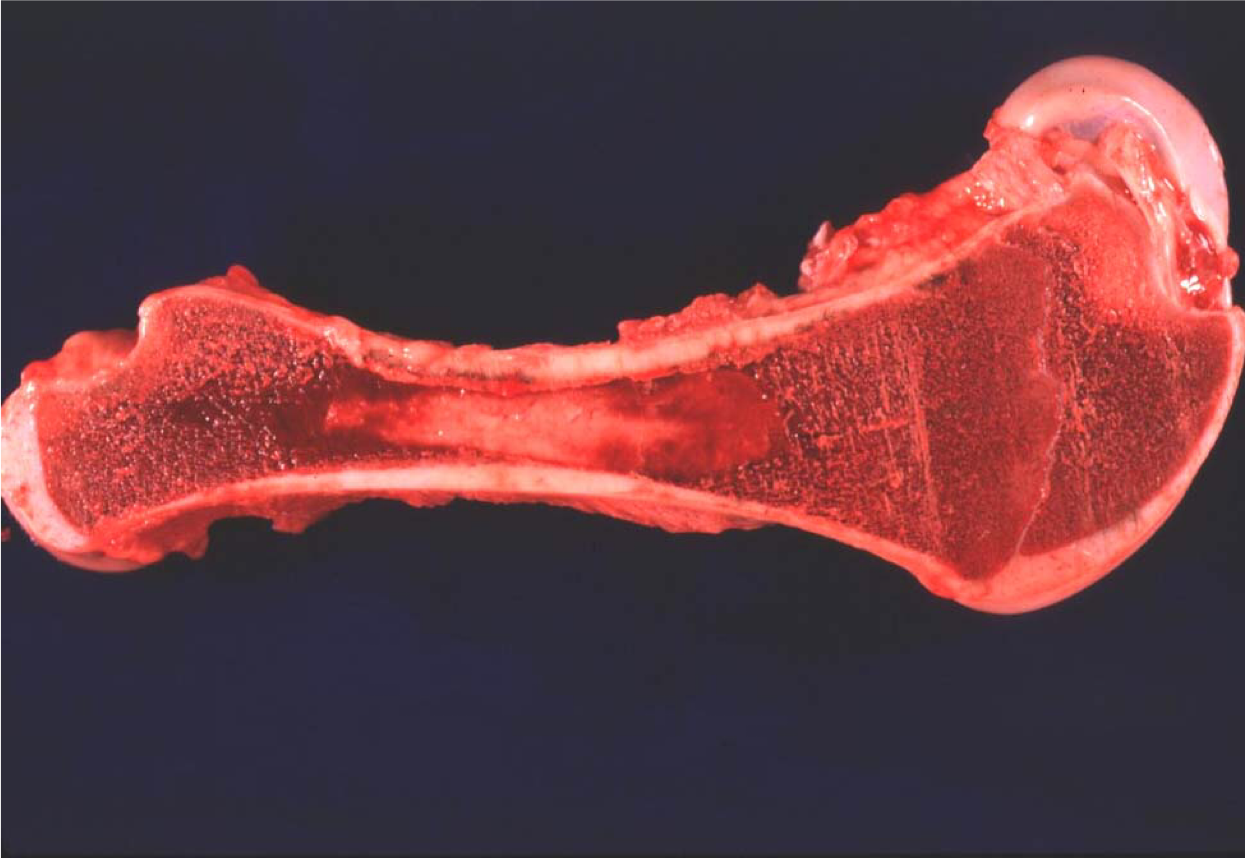

Replacement of yellow marrow by red marrow at the metaphysis and endosteal surface of the diaphysis indicates what process?

Marrow hyperplasia